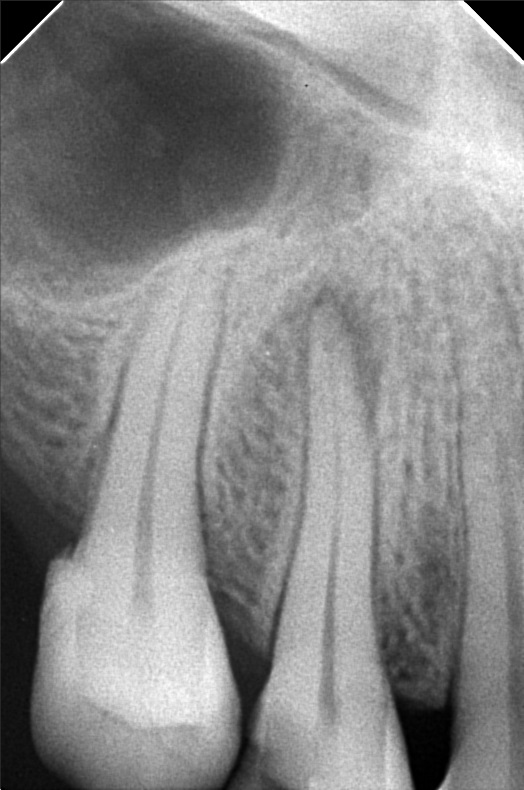

Edit Record Check our patient data records. Add patient information Patient Info Profile picture Last Name First Name Middle Name Birthdate Age Street Barangay City Country Zip Code Contact number Email Procedure 3/22/22- OP Lc 13 m/ 21 d/ 22 m/ 47 o/ b/ cervical xray 14 for rct 10/11/22 - OP (L); ACCESS #14, SCOUT #10 BL 18mm, EUGENOL. 10/14/22- 12/11/21/22- TF emax veneers 10/19/22 - 19mm, close w/ pulp devitalizer 09/02/23- op ** For change of crowns posterior Lower for Crown #15 08/13/24 OP 01/23/26 Alumina crwon #14 temporary crown OP Scanning File bangaros.jpg File 2 bongaros.jpg File 3 bongaros_02.jpg File 4 bongaros_03.jpg File 5 bongaros_04.jpg File 6 309497615_1081002115924778_349479569281481267_n.jpg File 7 bongaros_1.jpg File 8 bongaros_02_1.jpg File 9 File 10 File 11 File 12 File 13 File 14 File 15 File 16 File 17 File 18 File 19 File 20 Retain Record Retain Record Yes No Save Your Changes